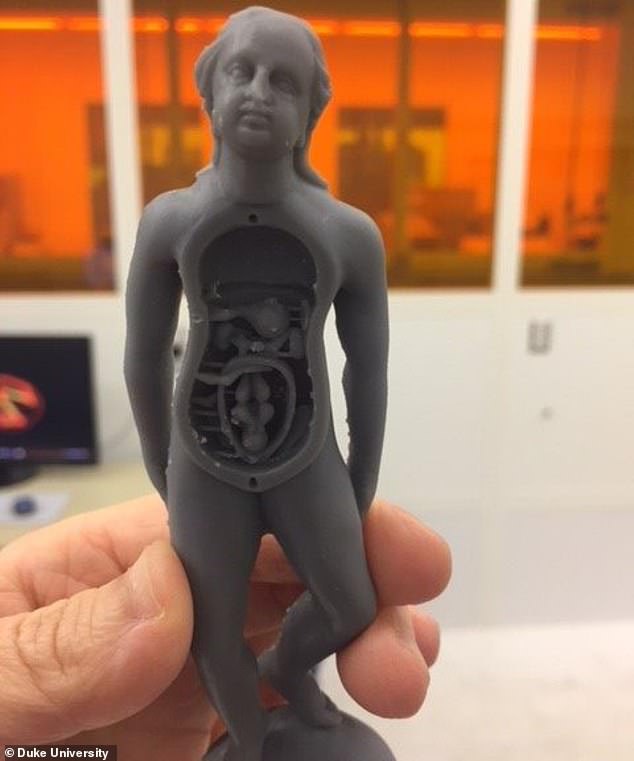

وأشار الباحثون، إلى أن أغلبية التماثيل تصورأجساد النساء ويمكنك فتح بطنها فتجد "الجنين" المتصل بحبل من النسيج، مضيفين أن الاقزام استخدموا في دراسة علم التشريح الطبي وربما حتى لدراسة الحمل والولادة.

وقام الباحثون الأمريكيون، بمسح الأجزاء الداخلية لـ 22 من التماثيل وكشفوا عن تفاصيلها من الداخل، لافتين إلى أنهم سوف يقومون بإنشاء نماذج ثلاثية الأبعاد للعارضين من أجل التفاعل بشكل أفضل مع القطع الفريدة من التاريخ الطبي دوت التعرض لخطر التلف.

ومن خلال إجراء عمليات المسح الضوئى ثلاثى الأبعاد للعارضين، تمكن الدكتور شوارتز وزملاؤه من معرفة المزيد حول كيفية صنع التحف الطبية – ويأملون فى نسخ تماثيل متماثلة ثلاثية الأبعاد يمكن للجمهور التفاعل معها بالفعل، غالبًا ما تستخدم الأشعة السينية والأشعة المقطعية - كتلك المستخدمة في المستشفيات - لفحص القطع الفنية الهشة أوالقديمة، والتي يمكن استخدامها دون الإضرار بالموضوع.

تمثال لسيدة وبداخلها جنين